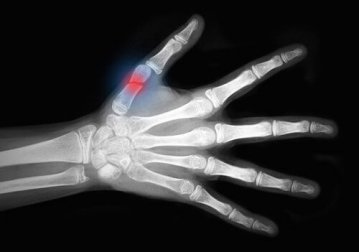

Uma fratura óssea, tanto completa quanto parcial, é um grande trauma para o corpo. Felizmente, o nosso organismo tem a capacidade de regenerar o tecido ósseo, mas às vezes este é um processo lento.